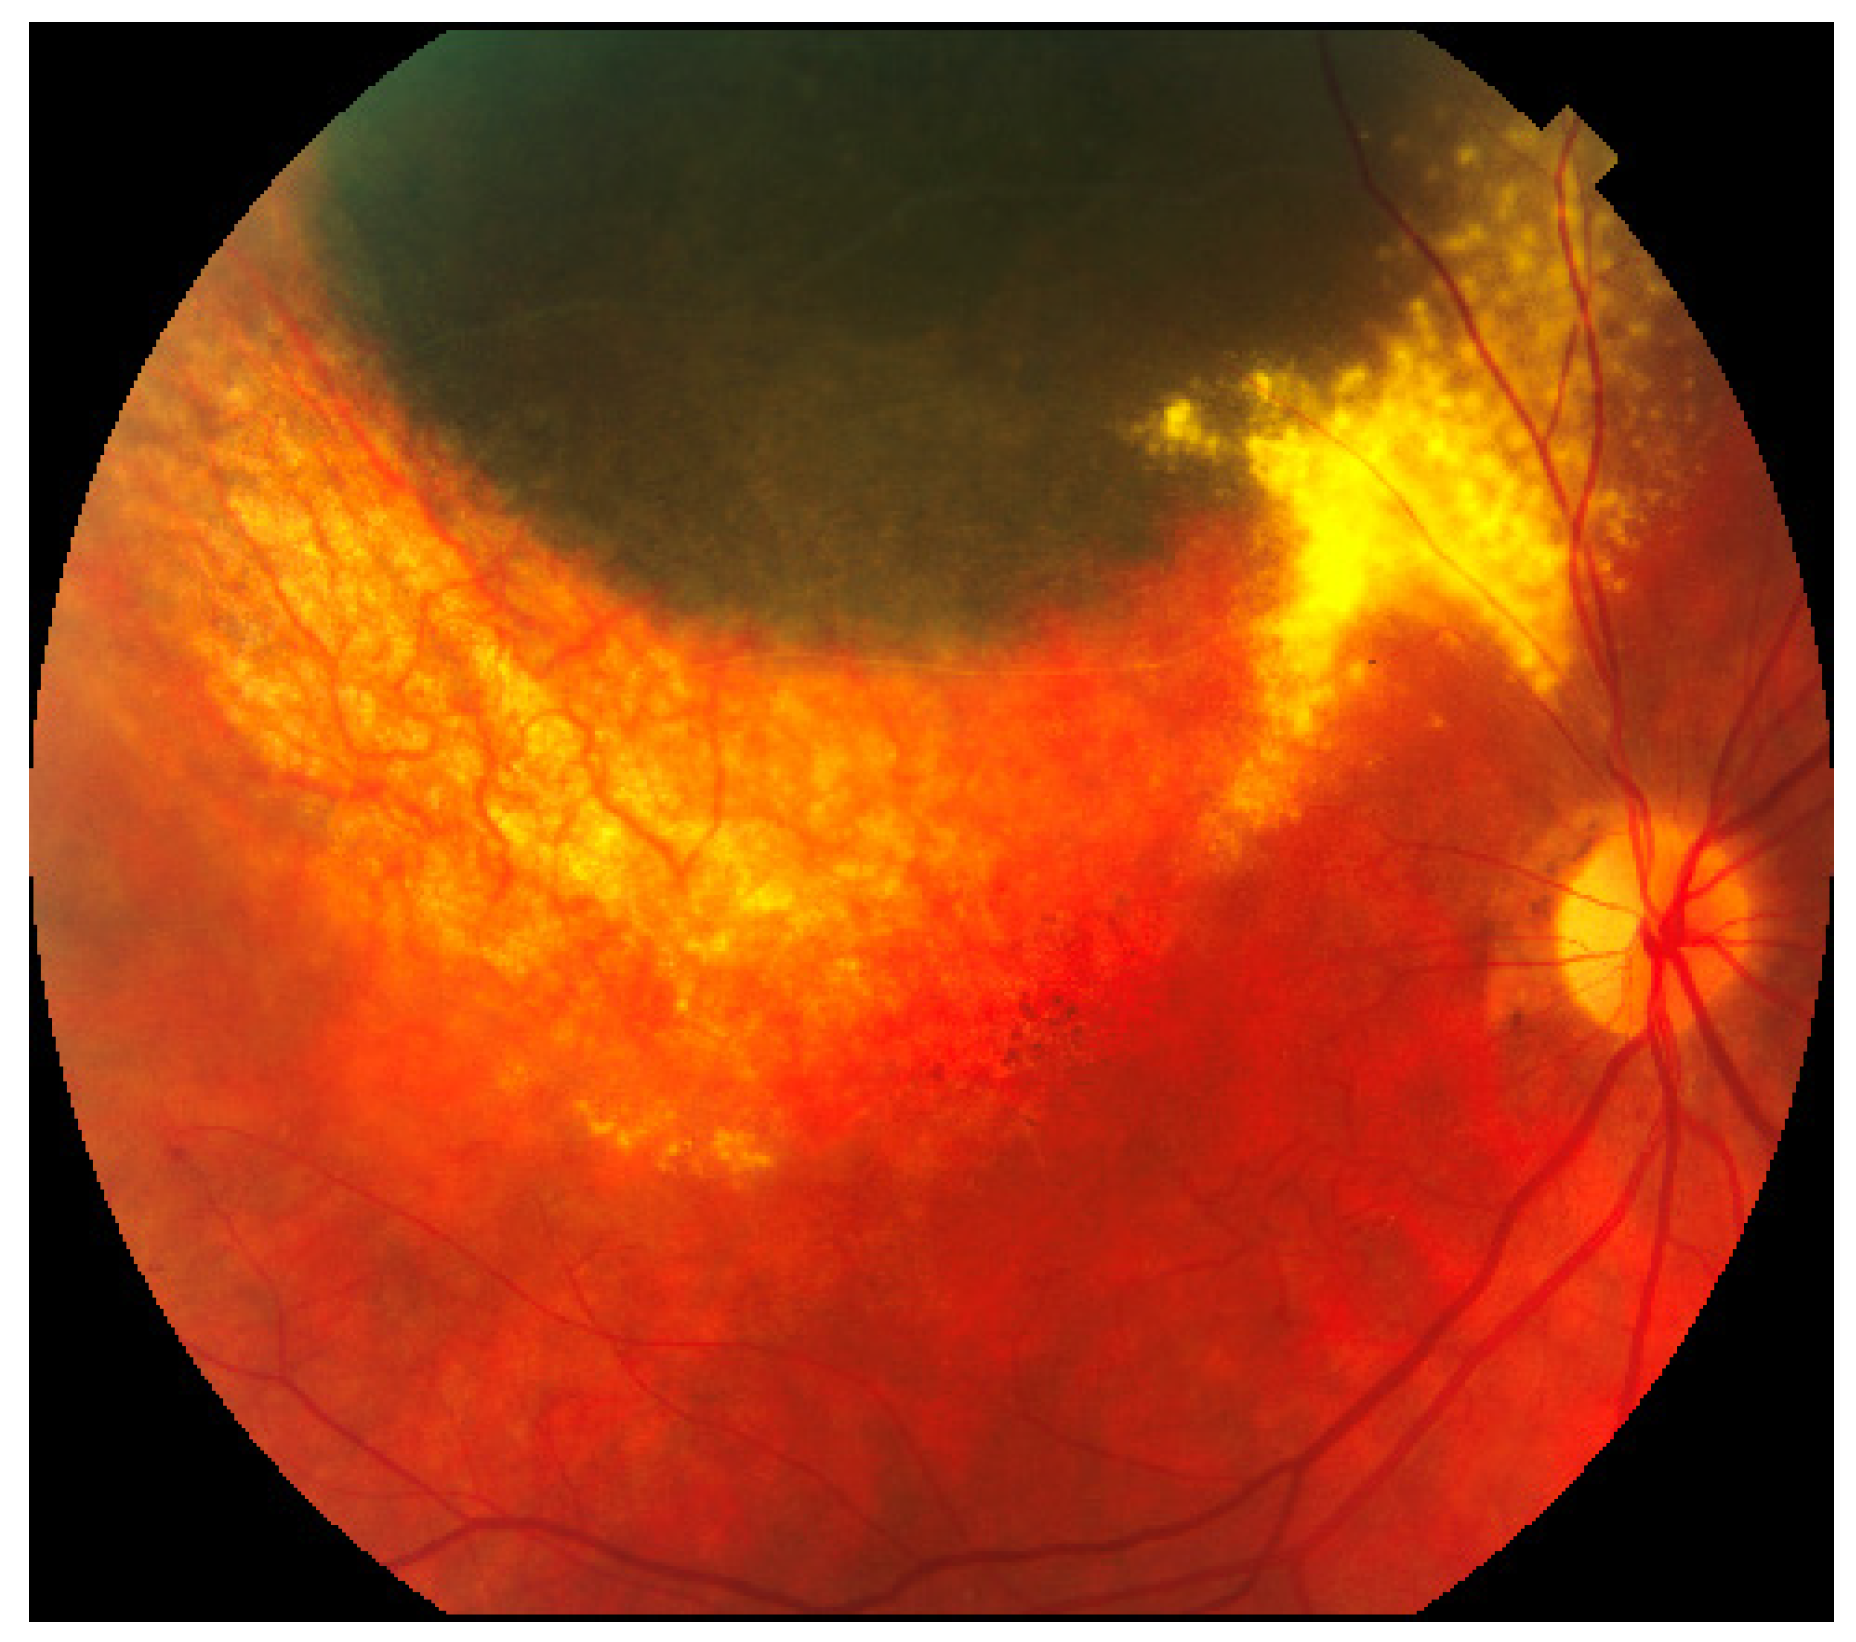

3.1. Radiation (Chorio)Retinopathy